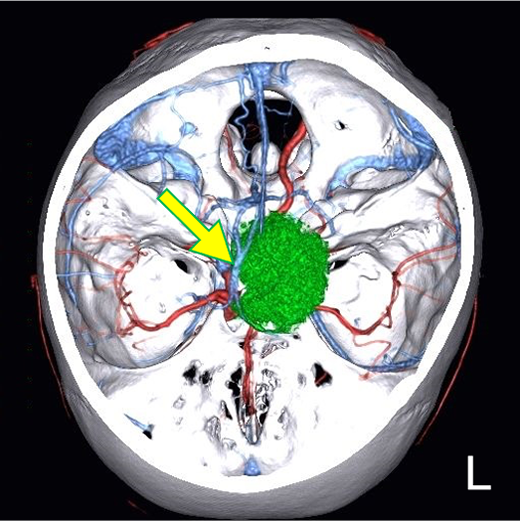

図7.造影後T1WI、4D-CTAngiographyのFusion像

thalamostriate vein, internal cerebral vein(矢印)を圧排する病変(緑)を認める。

1. 本症例は神経膠腫や悪性リンパ腫などとの鑑別も必要となる実質内腫瘍であるが、診断を進めるうえで、病変の形態や内部性状の把握のための検査として、造影MRIの役割がある。

2. 生検実施に際して使用するニューロナビゲーターのデータとして、精細な造影MRIは必要かつ有用である。術前検討のFusion 像においても、造影される病変と血管の位置関係の把握が可能であった。脳深部の病変へ確実に到達するために、手術支援の見地から造影MRIは有用な検査である。